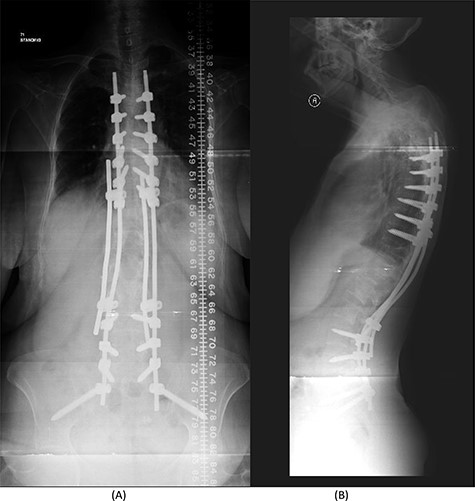

The bridging technique was used to achieve relative stability through posterior fixation until the anti-TB medications cleared the vertebral infection and allowed re-ossification of the destructed levels (T11–L3) to occur. An open biopsy was done intraoperatively to reconfirm the diagnosis of spinal TB. The patient started mobilizing early postoperatively and continued to take the anti-TB medications for 18 months (Fig. 4).

(A) AP lumbar spine X-ray demonstrating the bridging technique. (B) Lateral spine X-ray showing the bridging technique sparing the infected area.

The success rate of surgical TB management is high and effective according to a study based on data collected from 582 patients throughout 11 years [8]. Our patient presented with a destructive spinal lesion and underwent posterior spinal decompression and instrumentation of T11–L3. Nevertheless, due to severe destruction, loosening and poor bone quality of the levels T11–L3, along with the multiple medical comorbidities, anterior surgical intervention with a thoracoabdominal approach with resection of all the levels involved would associate with major morbidities and complications. To achieve a balanced construct and to have multiple fixation points, which was needed to overcome the poor bone quality, the fixation was done from T5 down to the pelvis (Fig. 4), spanning the destructed area and utilizing the bridging technique with multiple rod constructs across the T11–L3 region.